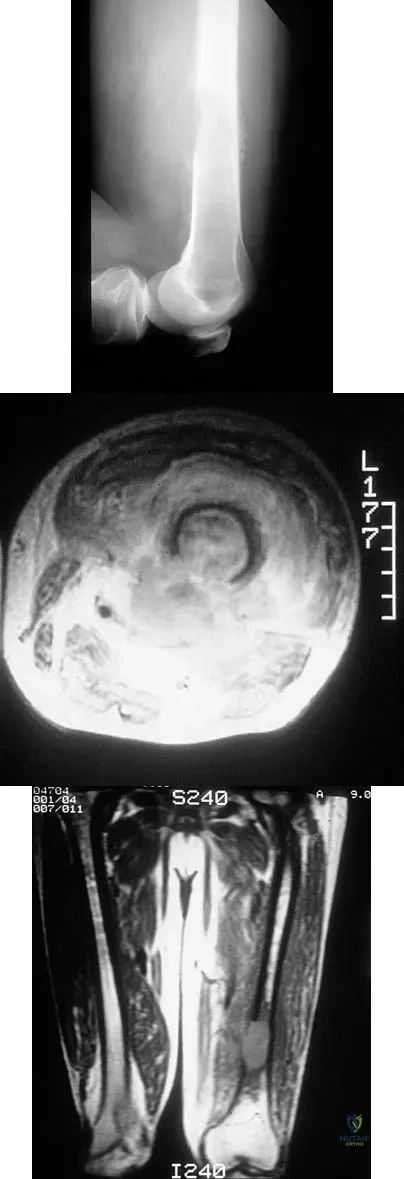

A 13-year-old boy has had pain and swelling in his ankle for the past several months. Based on the radiograph, MRI scan, and biopsy specimen shown in Figures 77a through 77c, what is the best course of action?

Figures 48a through 48c show the lateral radiograph and MRI scans of a 60-year-old man who has had pain in his thigh for 1 month. The next most appropriate step in management should consist of